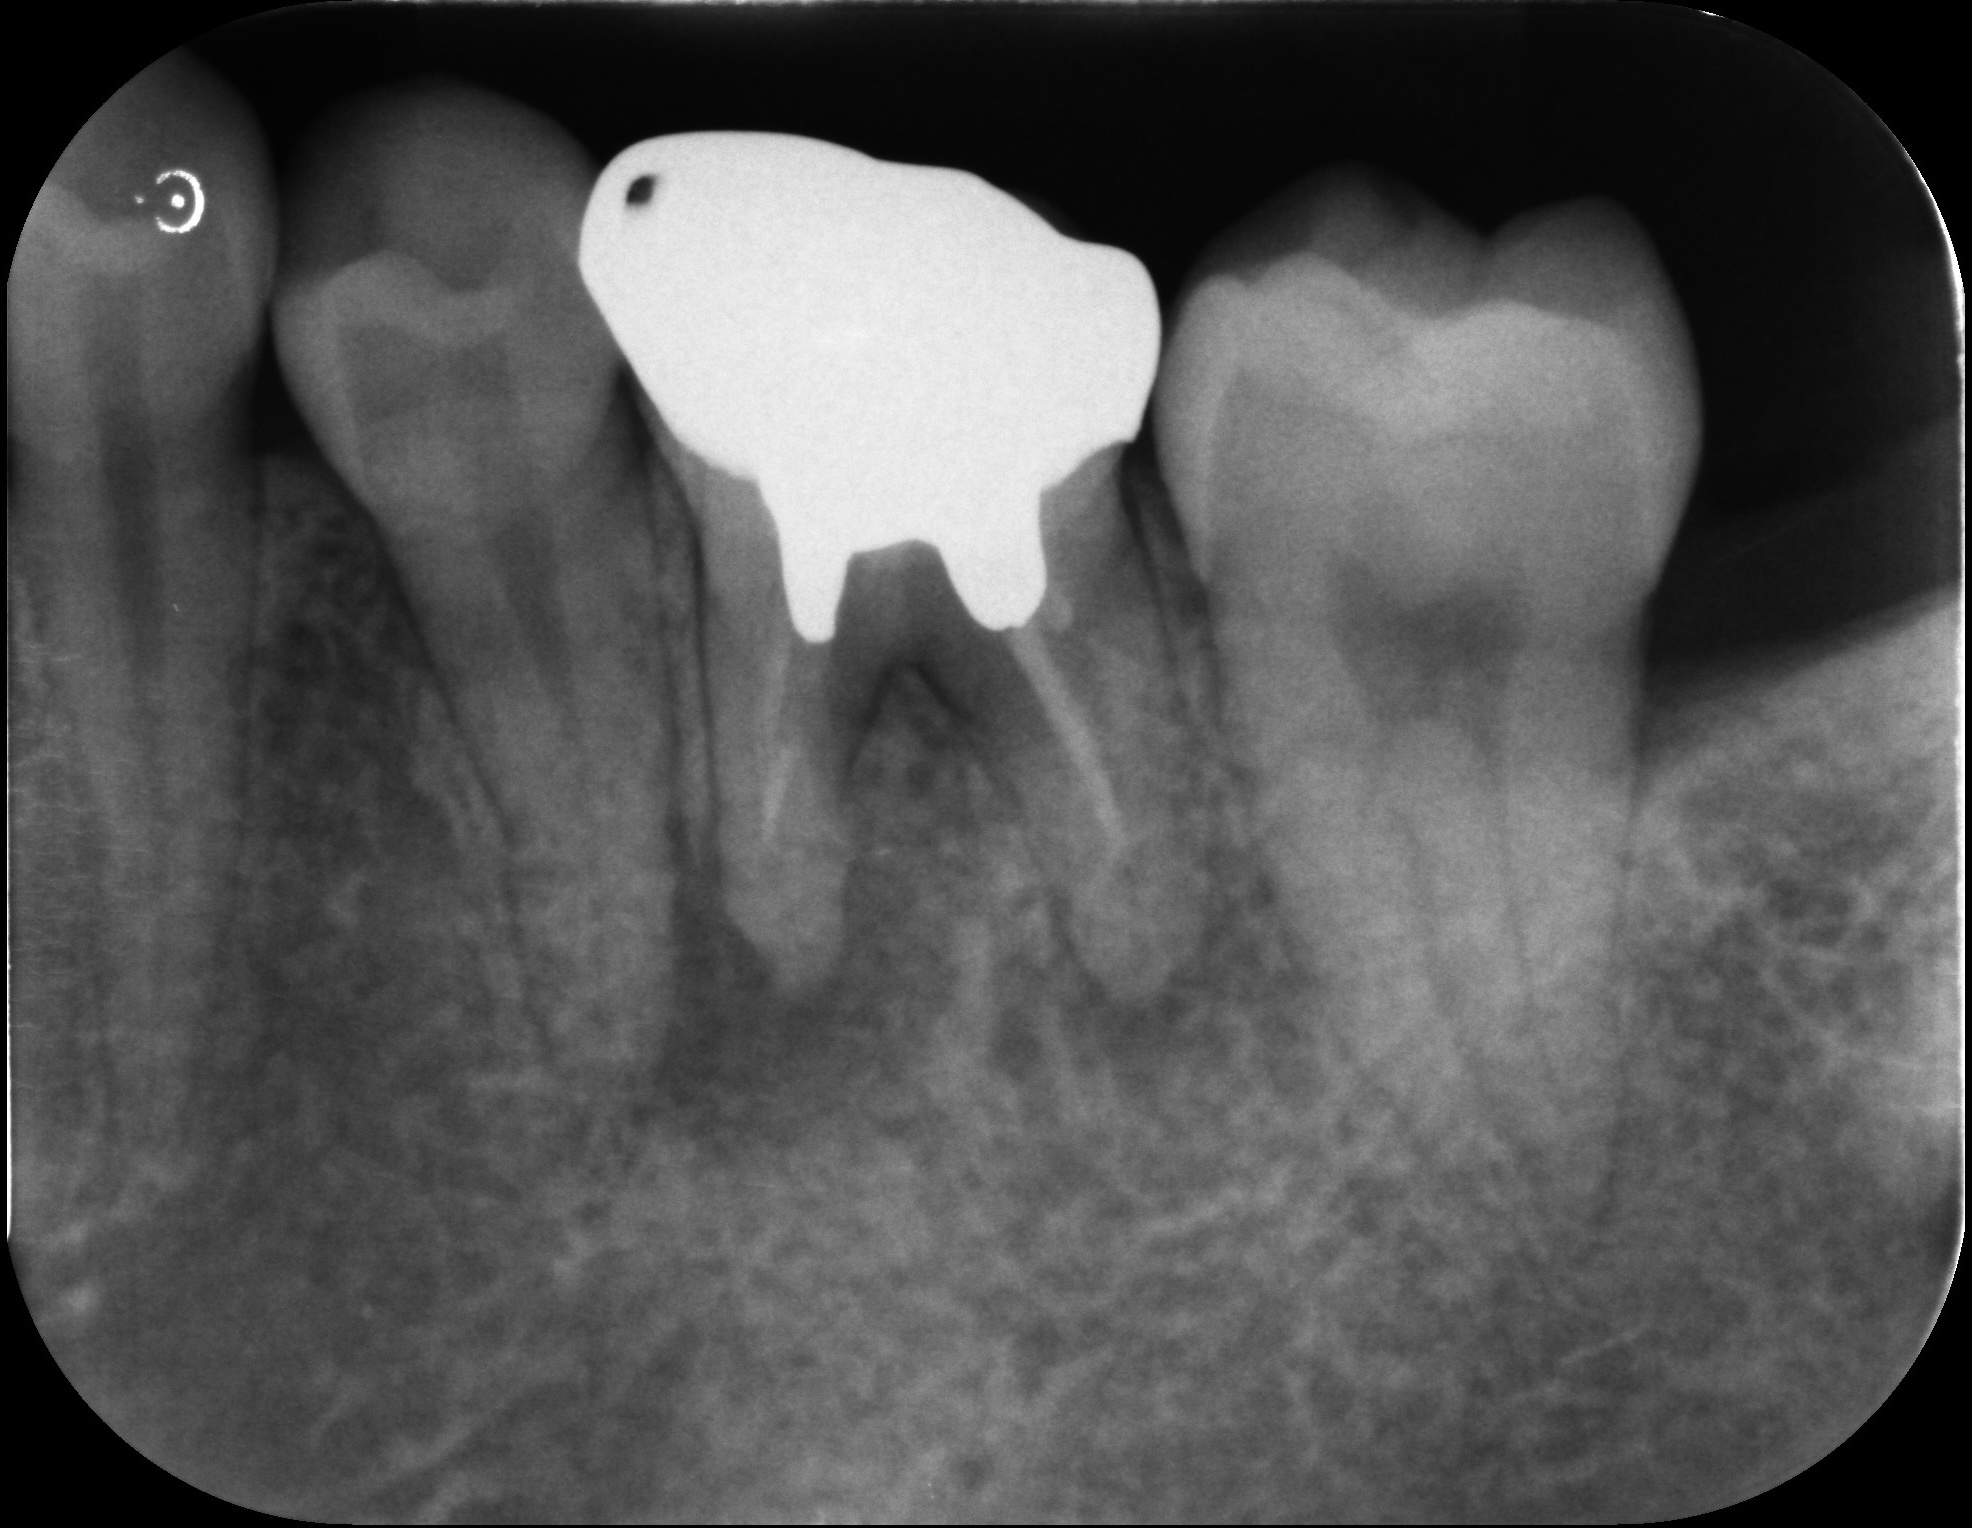

大臼歯の再根管治療を行った症例

タップで写真の拡大ができます。

Before&After(根管治療)

Before

Before&After(根管充填)

主訴

歯茎が腫れて、噛むと違和感がある

治療内容

再根管治療(大臼歯)

治療期間

1ヶ月

治療費用

165,000

治療の

リスク

処置中に歯肉縁下におよぶ重度のう蝕や破折を認めた場合、治療を中断する可能性があります。術後も症状が残る場合は追加の処置が必要になる可能性があります。